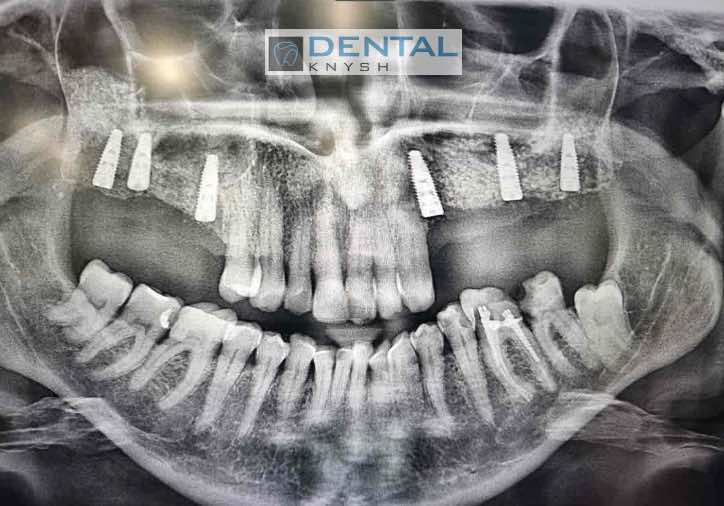

Сканы КТ имплантации зубов, 2026-04-18

Скан КТ, 2026-04-18

Сканы КТ имплантации зубов, 2026-04-18

Скан КТ имплантации зубов, 2026-04-17

Сканы КТ имплантации зубов, 2026-04-18

KT: имплантация зубов DentalKnysh, 2025-01-03, сканы

KT: имплантация зубов DentalKnysh, 2025-01-03, сканы

KT: имплантация зубов DentalKnysh, 2025-01-03, сканы

С 2023-09-05 по 2023-09-09 сканы КТ от 6 до 12 имплантов в DentalKnysh (4 фото):

Синуслифтинг и имплантация зубов, 6 имплантов, all-on-6, КТ скан 1, 2023-08-31

Фото отчет Имплантация зубов, 6 имплантов, КТ скан 3, 2023-08-31

Фото отчет Имплантация зубов, 8 имплантов, all-on-4, КТ скан 1, 2023-08-31